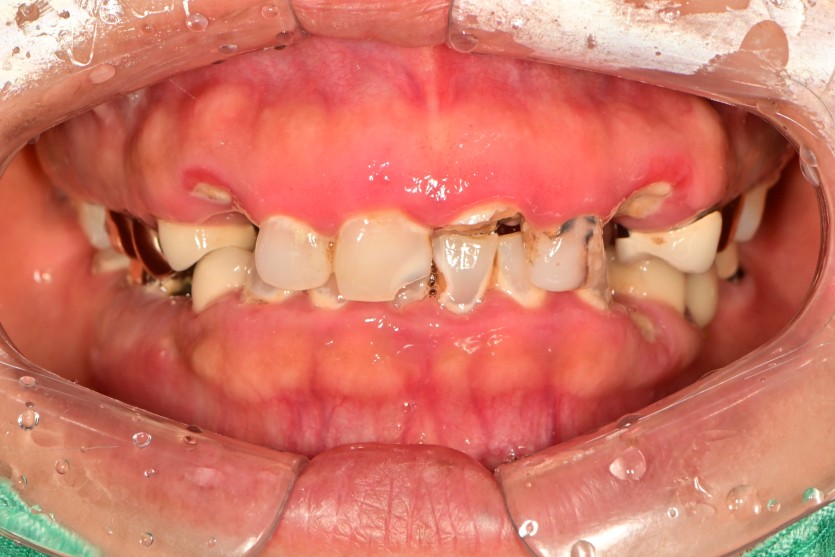

만 56세 전체 임플란트 증례

전체 임플란트 증례입니다.

17개의 임플란트로 완성하였습니다.